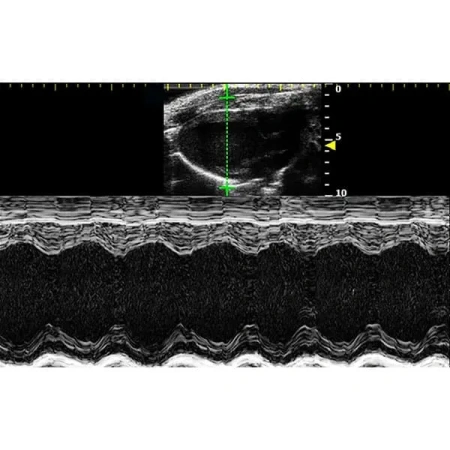

Благодаря неинвазивной и экономичной конструкции RevoSilex идеально подходит для повторных измерений в ходе долгосрочных исследований. Он обеспечивает точный мониторинг структуры, функции и гемодинамики сердца, что делает его незаменимым для исследований сердечно-сосудистых заболеваний и тестирования лекарств. Возможности цветного допплеровского картирования системы еще больше повышают ее полезность при оценке кровотока и выявлении ранних маркеров заболеваний.